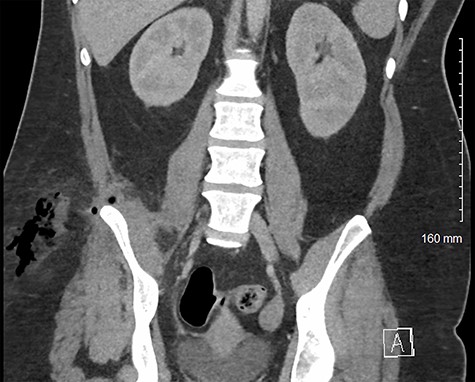

A normally fit and well 33-year-old woman presented to the emergency department with right flank and thigh pain for 3 weeks. She had previously been seen in primary care following 1 week of thigh pain, which was initially attributed to a musculoskeletal cause for which she was advised to take simple analgesia. The patient returned to the emergency department when the pain significantly worsened, and she developed an associated fever. Apart from a high body mass index, she had no other co-morbidities. On examination, she had diffuse erythema and tenderness over her proximal thigh, particularly marked on the medial aspect (Fig. 1). The erythema extended to her ipsilateral iliac crest. There was no palpable fluctuance or crepitus. Pain was exacerbated by movement at the hip joint, but there was no reduction in the range of movement. There was no guarding or tenderness on abdominal examination. At this time, her temperature was 39.3°C. She was tachycardic at 152 beats per minute but was normotensive, with a blood pressure of 111/57 mmHg. Her respiratory rate was 19, and she was saturating at 96% on air. Her white cell count was 19.2 (109/l), and her C-reactive protein was 148 (mg/l). She was scheduled for immediate surgical exploration of the flank and thigh under the plastic surgery team as necrotizing fasciitis could not be excluded. Given the atypical presentation, a prompt computed tomography (CT) scan of the abdomen and pelvis prior to surgical exploration was undertaken. This demonstrated large volume subcutaneous emphysema in the soft tissues of the thigh and flank. This was associated with a fistula tracking superior to the right iliac wing, originating from an appendiceal collection involving the iliacus muscle and the pelvic sidewall (Figs 2 and 3).

Coronal CT image of patient’s pelvis/abdomen demonstrating fistula tract containing gas and fluid from the intra-abdominal space through the inferior lumbar triangle into the soft tissue of the flank/proximal thigh.